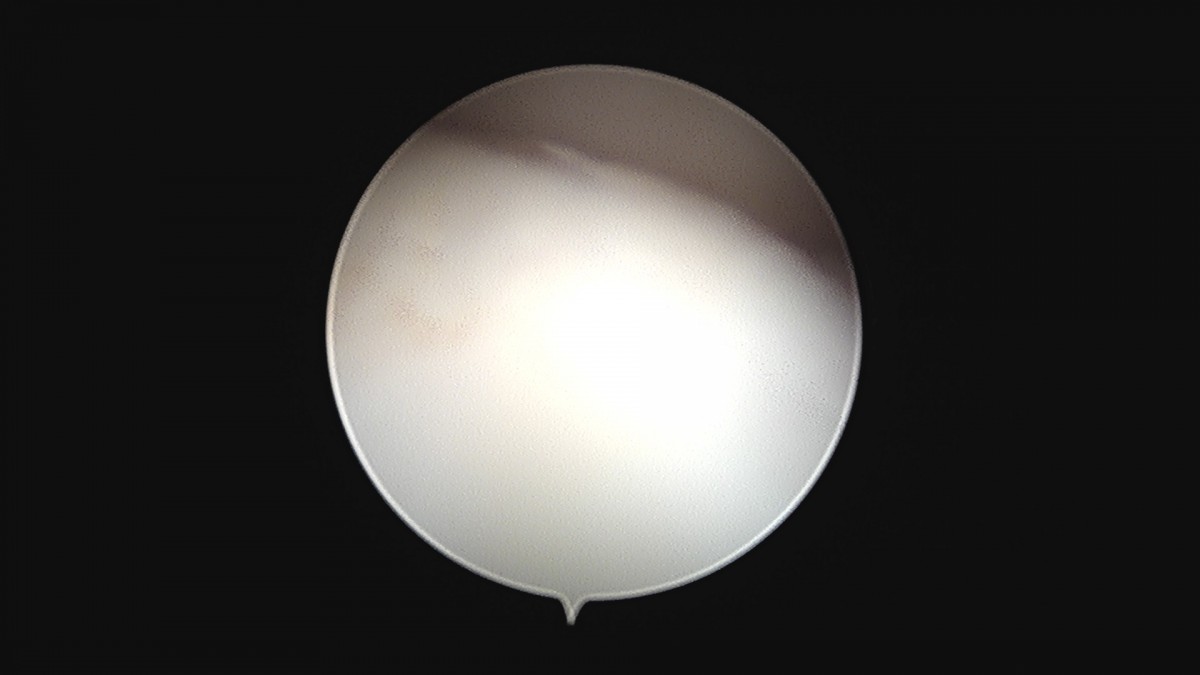

이재상원장님 무릎 변연절제술 권오O 환자

작성자 최고관리자 댓글 0건 조회 373회 작성일 25-09-16 16:11